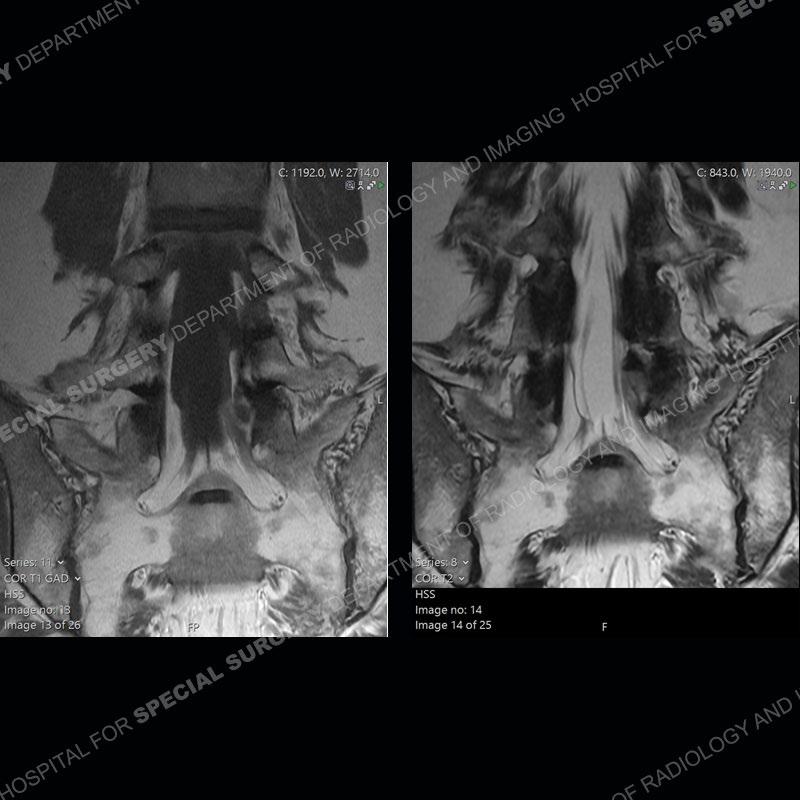

Post operative changes are seen on the left side at L5-S1 where there is near complete removal of the left sided L5 lamina, partial resection of the left L5-S1 facet joint, and resection of the left sided ligamentum flavum. In the anterolateral epidural space about the subarticular recess is a mass that demonstrates similar T1 and T2 signal characteristics to the adjacent degenerated disc. There is enhancement about the periphery of the mass, but the majority of this somewhat geographic or polyploid mass demonstrates no enhancement. The mass exerts prominent mass effect on the left S1 axillary sleeve/proximal nerve root. The left S1 nerve root shows enlargement and increased enhancement as compared to the contralateral right side.

Not as much of a diagnostic dilemma as some other cases but more so just a very nice example of what can be a difficult assessment at times. The evaluation of granulation tissue/scar/epidural fibrosis vs. disc herniation particularly in the earlier post operative period can be very difficult. Clues that can assist in identifying a disc herniation are a more geographic or polypoid nature to the mass, signal characteristics similar to the adjacent degenerated disc, mass effect upon the thecal sac/adjacent neural structures, and a typical enhancement pattern. As the disc material is avascular, as long as imaging is performed in a relatively rapid fashion after contrast administration (within 20-30 minutes), the granulation tissue around the disc will enhance but the disc material itself will not. If there is a marked delay between contrast administration and imaging, there may be diffusion of contrast into the disc making the assessment very difficult. The marked utility of contrast to help delineate disc vs. scar has led to our institution employing contrast fairly uniformly within the first two years following surgery.

The scar tissue in the setting of prior disc removal will be present in the anterior and anteriorlateral aspect of the epidural space. The signal characteristics can be somewhat variable from slightly more T2 hyperintense earlier on to T2 hypointense as the scar matures. However, the signal does not tend to follow the adjacent degenerated disc. The scar can produce mass effect, but it does not have to do so. In addition, at times the scar may be associated with a retraction of the adjacent thecal sac. Given the vascular nature of the scar there is typically somewhat avid, uniform enhancement which occurs fairly rapidly after contrast administration and begins to diminish within 20 minutes or so. Trying to discern the difference between scar and disc is of paramount importance given the rather poor outcomes associated with resection of scar as compared to disc material.